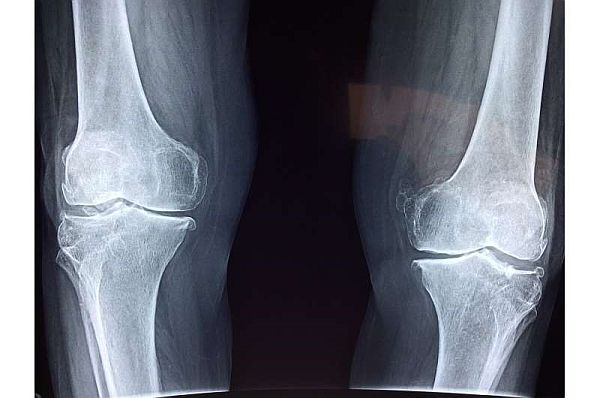

Những thử nghiệm từ các phòng thí nghiệm khác hoạt động với EGFR đã cho kết quả "khó hiểu và gây tranh cãi". Nhưng phòng thí nghiệm của Ling Qin đã tìm ra mối liên hệ giữa viêm xương khớp và thiếu hụt EGFR, điều này tạo nên nền tảng cho giả thuyết của họ. Họ so sánh những con chuột điển hình với chuột có phân tử liên kết với EGFR, được gọi là phối tử, có biểu hiện quá mức trong tế bào chondrocytes, các khối tạo ra sụn. Sự biểu hiện quá mức này dẫn đến việc kích hoạt mạnh tín hiệu EGFR trong sụn đầu gối. Khi kiểm tra chúng, chuột có HBEGF biểu hiện quá mức (phối tử EGFR) được phát hiện thường xuyên có sụn mở rộng, có nghĩa là nó không bị mòn đi như những con chuột có hoạt động EGFR bình thường. Hơn nữa, khi những con chuột này ở độ tuổi trưởng thành, sụn của chúng có khả năng chống lại sự thoái hóa và nhiều dấu hiệu khác của viêm xương khớp, ngay cả khi sụn chêm của chúng bị hư hỏng.

Để chứng minh thêm rằng EGFR được kích hoạt quá mức là lý do cho khả năng phục hồi của chuột, nhóm nghiên cứu phát hiện ra phương pháp điều trị bằng gefitinib, được tạo ra để ngăn chặn chức năng EFGR, đã lấy đi lớp bảo vệ chống lại sự thoái hóa sụn. Với tất cả những kiến thức thu được, họ đã hướng đến giải pháp điều trị lâm sàng tiềm năng. Trong một loạt thử nghiệm mới, họ sử dụng phương pháp trị liệu nano bằng cách gắn phối tử EGFR mạnh, biến đổi yếu tố tăng trưởng-alpha, lên các hạt nano tổng hợp, để tiêm vào những con chuột đã bị tổn thương sụn ở đầu gối.

Khi những con chuột được tiêm liệu pháp nano này, đã làm chậm quá trình thoái hóa sụn và cứng xương, cũng như giảm đau đầu gối. Và không có tác dụng phụ lớn nào được thấy ở những con chuột được điều trị.